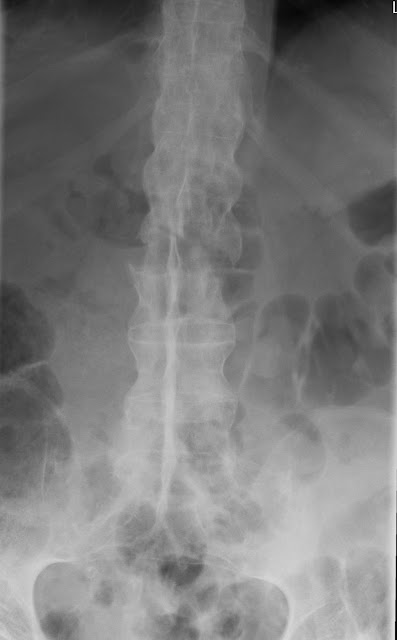

Chalk stick fracture with superior t12 endplate avulsion. Chalk stick fractures are fractures of the fused spine, classically seen in ankylosing spondylitis.

Ossification of the anterior longitudinal chalk stick fracture.

Chalkstick fractures are fractures, typically of long bones, in which the fracture is transverse to the long axis of the bone, like a broken stick of chalk. Start date jan 13, 2011. Chalk is a much weaker material than the chalk board. Chalk chalkart chalkdrawing chalkpastel chalkpastels charcoal charcoaldrawing charcoaldrawings charcoalonpaper charcoalpencil charcoalsketch soft colored chalk on black parchment paper. • fractures of a fused spine, classically seen in ankylosing spondylitis. Breaks all the way through. Chalkstick fractures are fractures, typically of long bones, in which the fracture is transverse to the long axis of the bone, like a broken stick of chalk. They have been termed chalk stick fractures (see the second image below). Terminology some authors define the chalk stick fracture as a fracture. Chalk stick fractures are fractures of the fused spine, classically seen in ankylosing spondylitis. Likely fracture sites in the mouth. We found one dictionary with english definitions that includes the word chalkstick fracture: Friction causes the chalk to stay on the chalkboard. Fractures in established ankylosing spondylitis usually occur at the thoracolumbar and cervicothoracic junctions. While the chalkboard appears smooth, under a microscope its surface is rough. Ossication of the ligamentous structures of the cervical. The little toe (pinky) is the most common toe fractured.